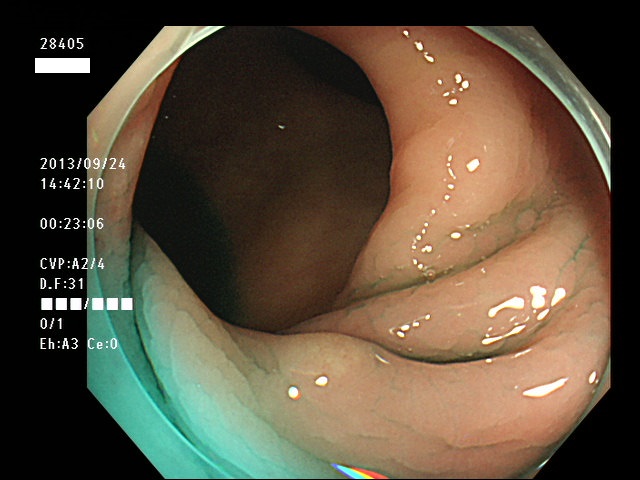

微小カルチノイドの診断

直腸の微小カルチノイドの診断は最も難しい問題です

微小とはいえ、カルチノイドは悪性であり、肛門に近い場所に好発するために、見落とすと数年後には「人工肛門」になる危険があります

進行したカルチノイドの診断は容易なのですが、カルチノイドは「粘膜下腫瘍」と言いまして、は表面が正常粘膜で被われているために微小ですと「単なる過形成結節」「単なる炎症性の隆起」と区別がつかないのです

下記の写真は全て、当院で診断された微小カルチノイド(悪性)ですが、いかに診断が困難かお分かりいただけるでしょう。このような微小病変でさえも見落とせば人工肛門の危険が潜んでいる訳です。